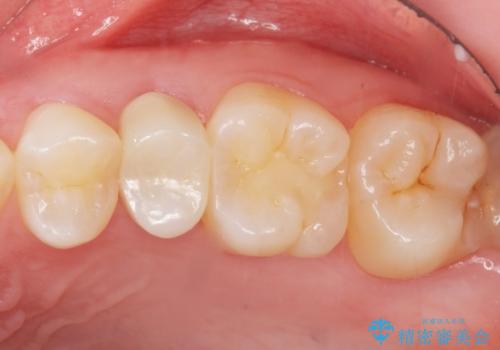

精査したところ、左上の小臼歯(左上5)は被せ物がないまま放置していたことにより、両隣の歯が寄ってきてスペースが少なくなり、また隣の歯(左上4)も虫歯になっていました。

隣の歯の虫歯治療(保険内のレジン充填)後、セラミッククラウンによる補綴を行いました。